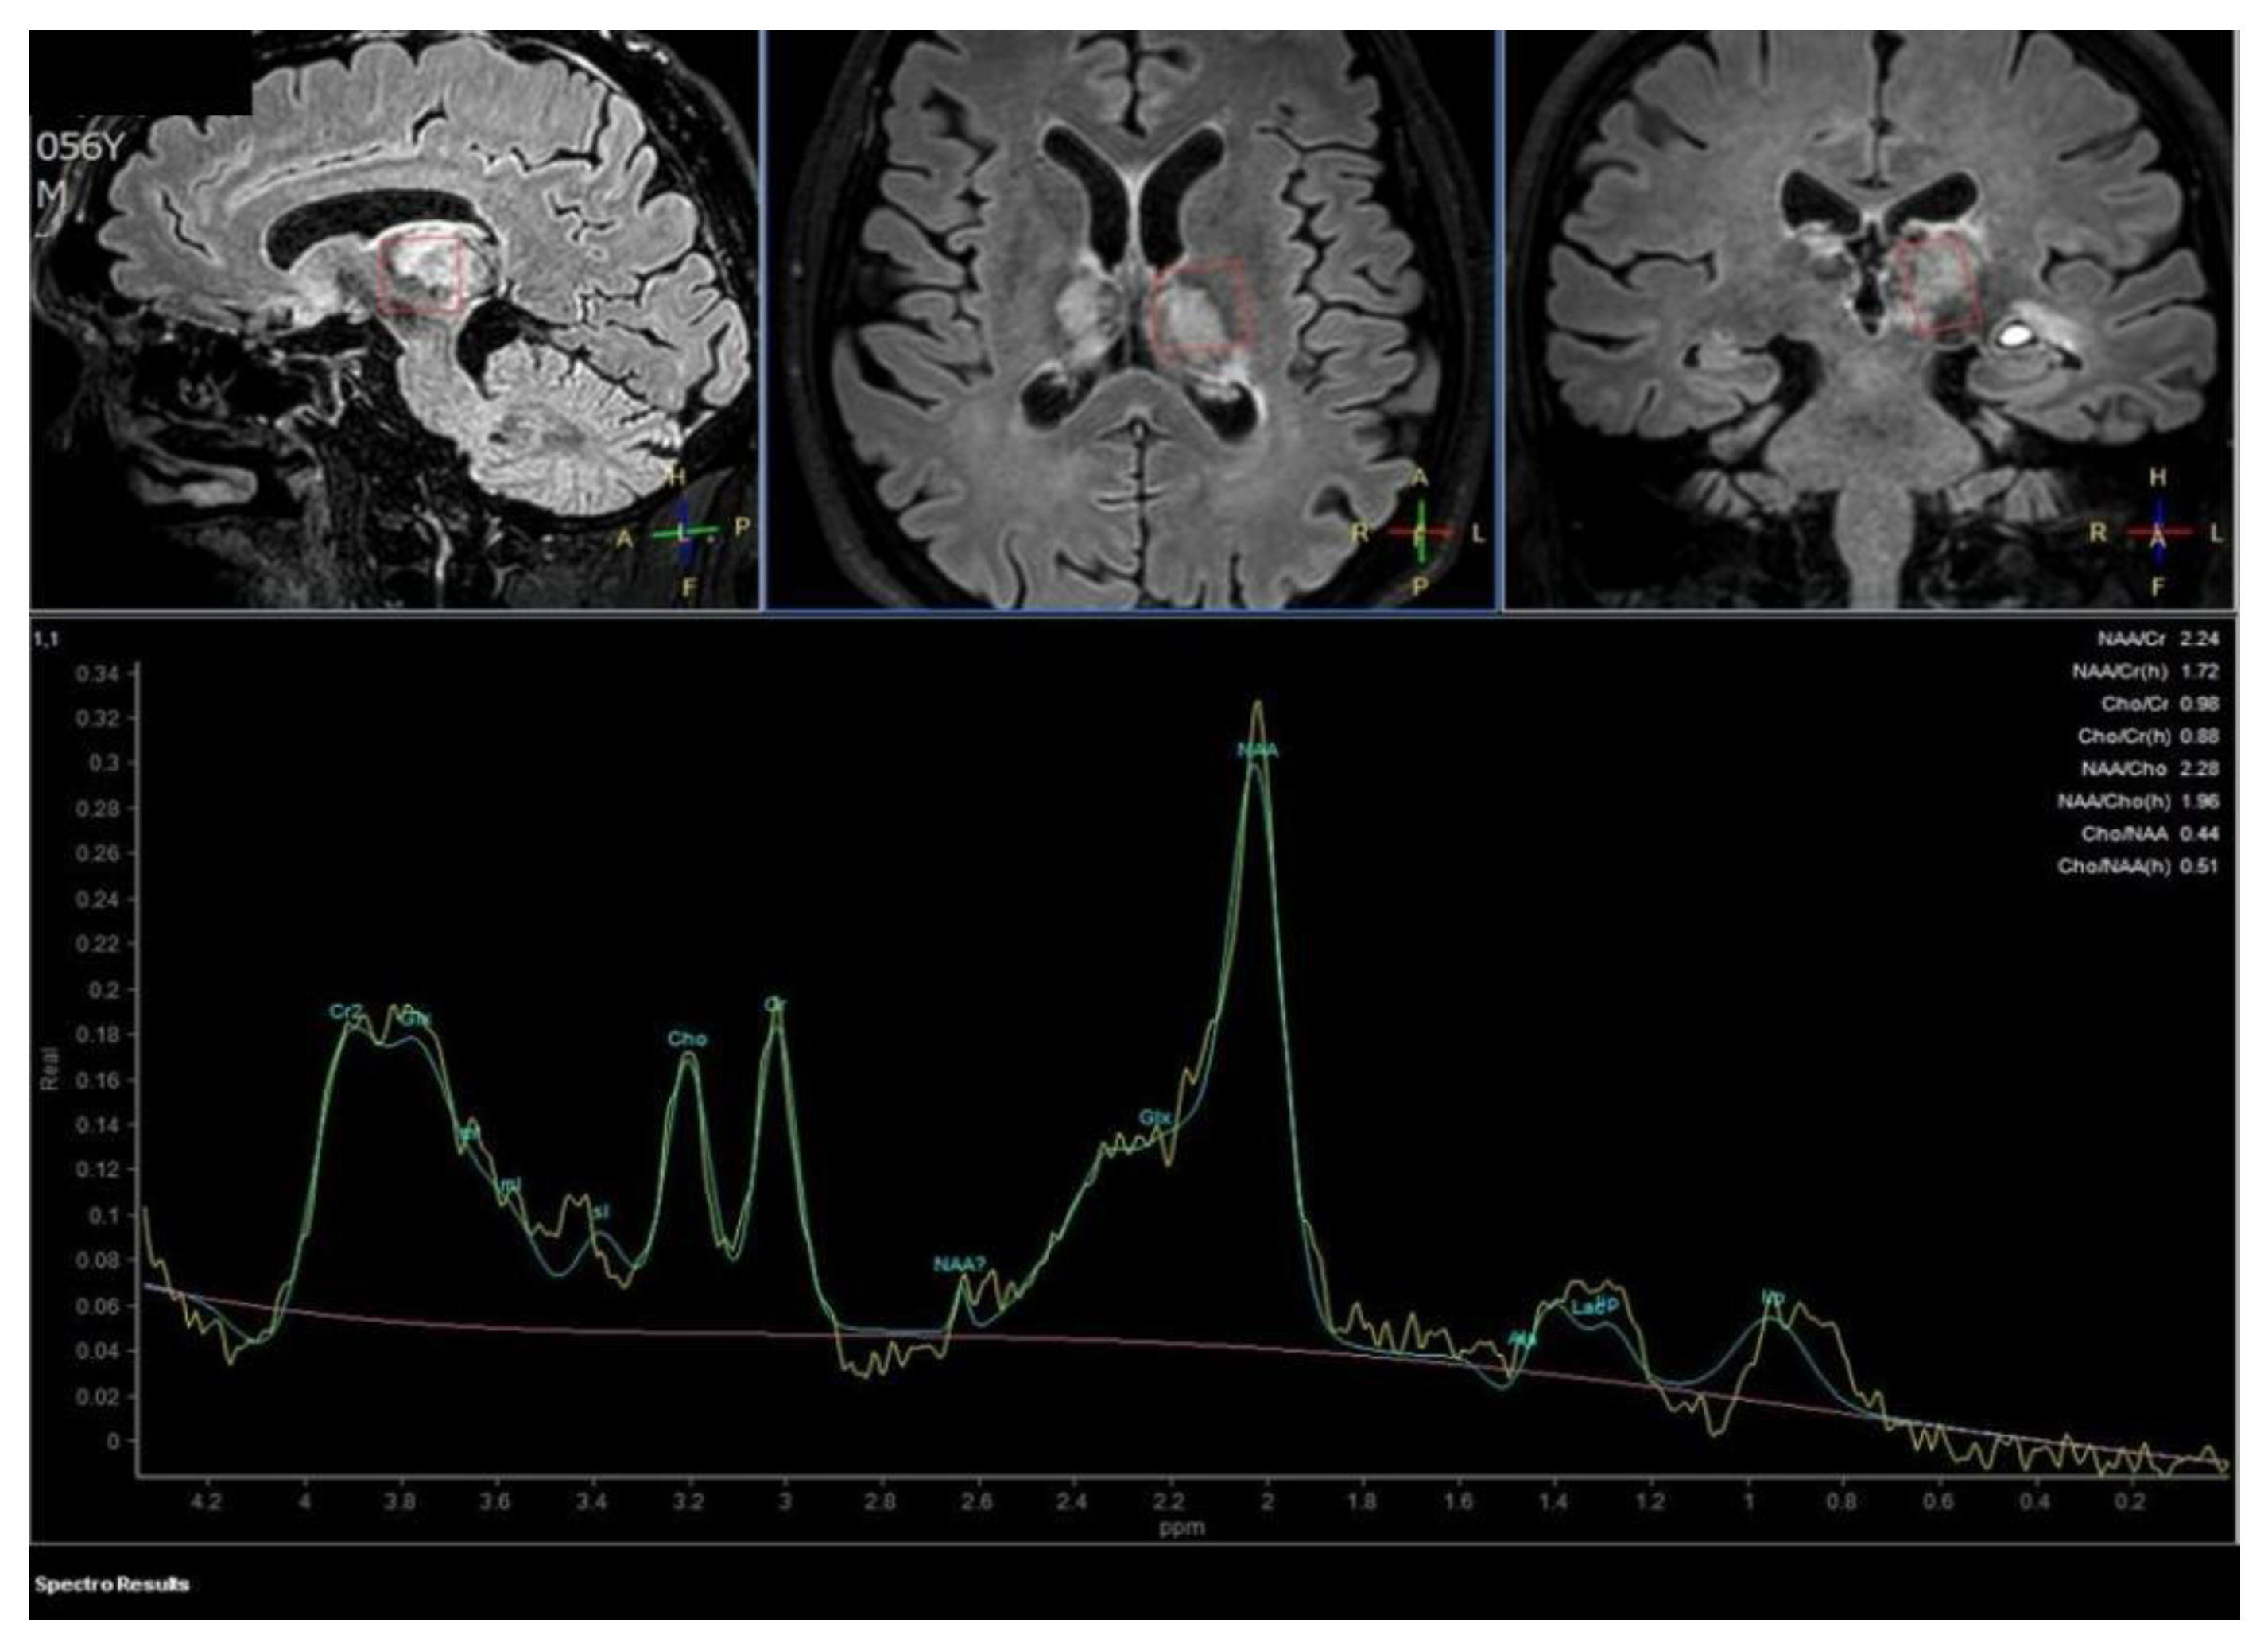

Proton MR Spectroscopy executed on the left thalamus demonstrates a normal spectrum of cellular metabolites, without anomalous metabolic peaks. The patient was soon candidate for anticoagulant therapy with Enoxaparin 6000 I.U./0.6 mL.